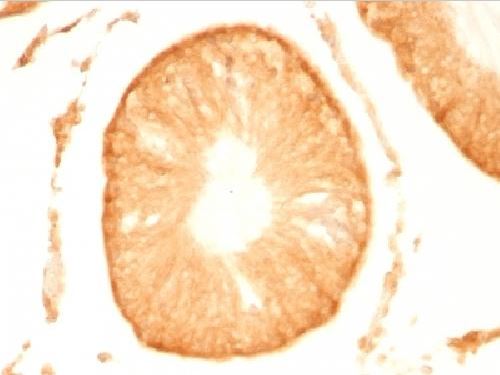

Immunohistochemistry (Formalin/PFA-fixed paraffin-embedded sections) - Alexa Fluor® 647 Anti-PGP9.5 antibody [EPR4118] - Neuronal Marker (AB196173)

IHC image of PGP9.5 staining in a section of formalin-fixed paraffin-embedded normal human pancreas*.

The section was pre-treated using heat mediated antigen retrieval with sodium citrate buffer (pH6) in a Dako Pascal pressure cooker using the standard factory-set regime. Non-specific protein-protein interactions were then blocked in TBS containing 0.025% (v/v) Triton X-100, 0.3M (w/v) glycine and 1% (w/v) BSA for 1h at room temperature. The section was then incubated overnight at +4°C in TBS containing 0.025% (v/v) Triton X-100 and 1% (w/v) BSA with ab196173 at 1/100 (shown in red) and counterstained using ab195887, Mouse monoclonal to alpha Tubulin (Alexa Fluor® 488), at 1/250 dilution (shown in green). Nuclear DNA was labelled with DAPI (shown in blue). The section was then mounted using Fluoromount®.

Image was taken with a confocal microscope (Leica-Microsystems, TCS SP8).